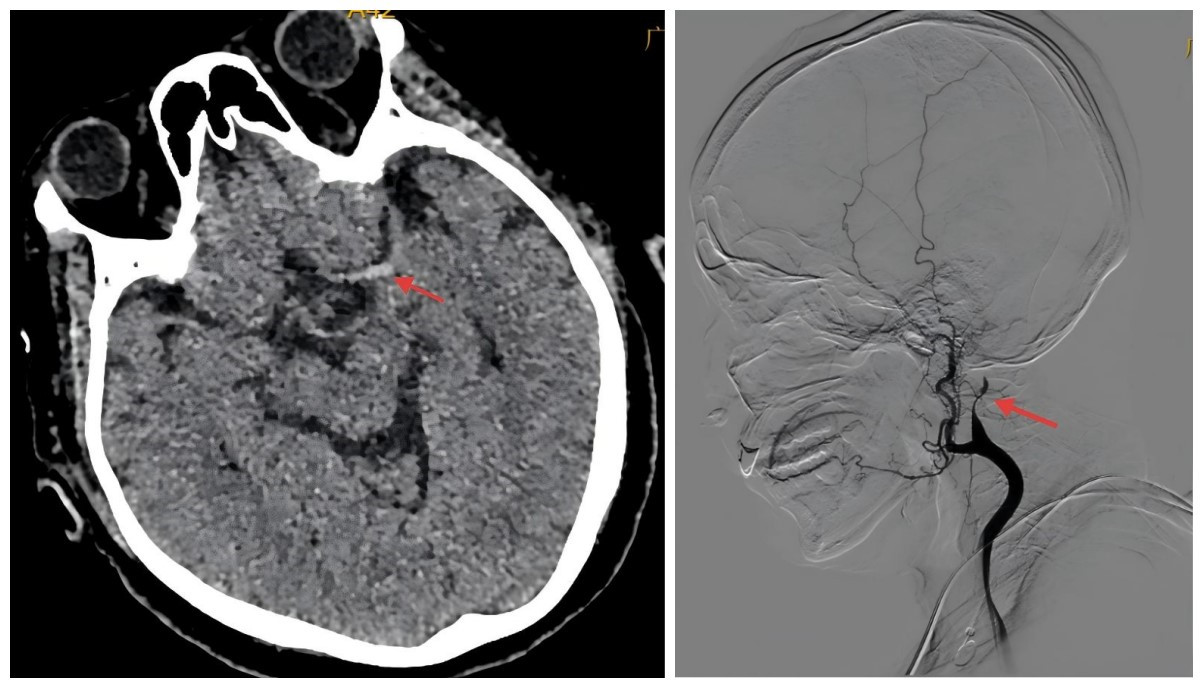

脑梗死介入取栓术

颈内动脉支架植入术

经桡动脉脑血管造影术

作为三级卒中中心,在经股动脉或桡动脉穿刺脑血管造影、缺血性卒中超早期静脉溶栓、动脉溶栓、急诊取栓、急性闭塞性血管再通技术、颅内外血管狭窄支架植入术等特色技术领域达到区内先进水平,为脑血管疾病患者提供全流程精准诊疗。